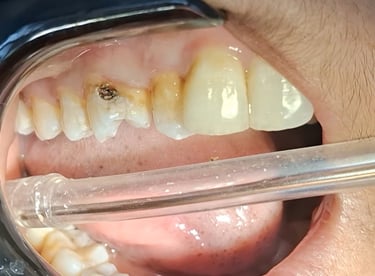

Tooth Colored Filling in Shyamal, Ahmedabad

Tooth-colored fillings are used to restore decayed or broken teeth while maintaining a natural appearance. These fillings blend seamlessly with your tooth color and help preserve your smile.

Before

After

All images shown here are real tooth colored filling cases treated at our clinic with patient consent.

At Shree Dental Care, cosmetic fillings are placed carefully with a focus on comfort, precision and long-term durability. We ensure minimal tooth cutting and natural-looking results.

If you are looking for aesthetic tooth colored filling in Shyamal, Ahmedabad, you can book an appointment with our clinic.